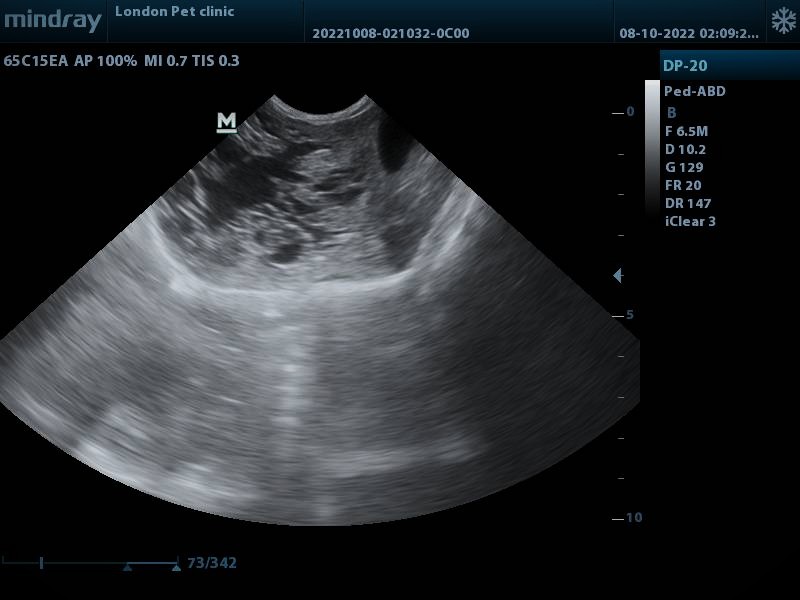

On presentation, A-Fast Scan shows the multiloculated cystic hepatic mass with thin septations and fluid-filled cavities; walls are smooth and well-defined.

• Ultrasound: Typically shows a multiloculated cystic hepatic mass with thin septations and fluid-filled cavities; walls are smooth and well-defined.